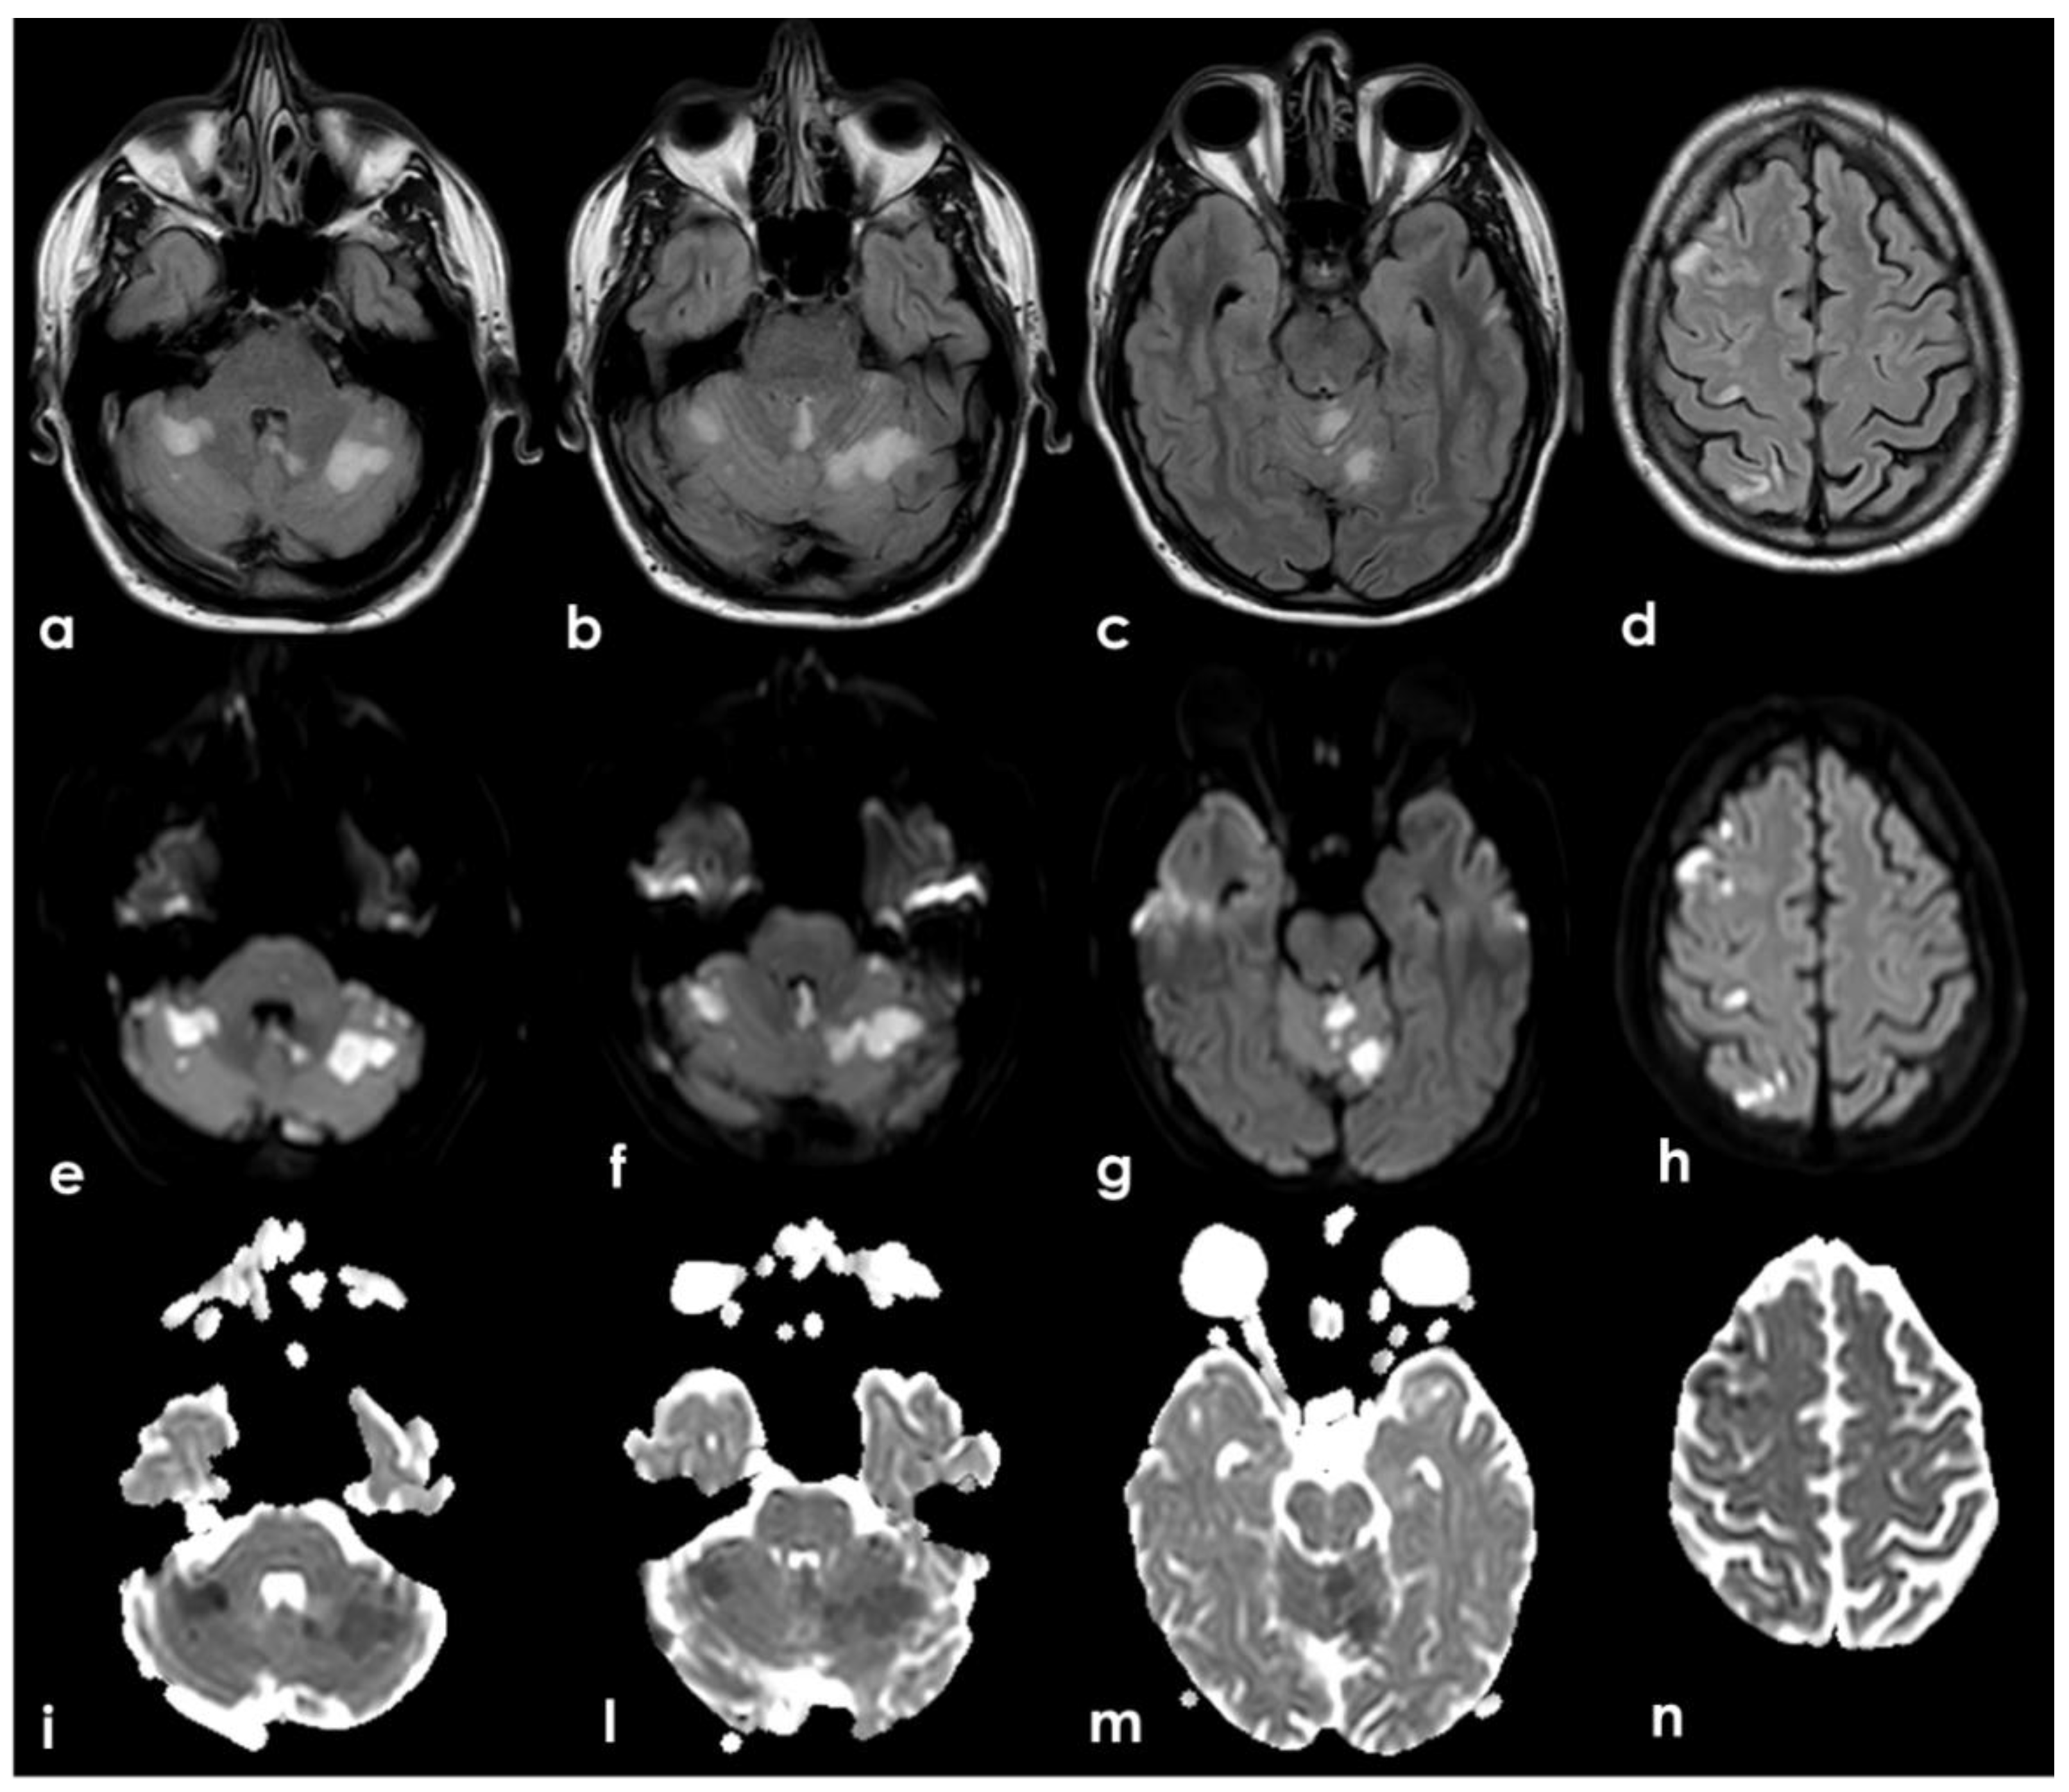

The presence of multiple subacute ischemic lesions already evident in the brain CT at admission excluded intravenous thrombolysis and endovascular treatment. Therefore, the patient was admitted to the Stroke Unit for acute stroke care and further investigations and started single antiplatelet treatment and low-molecular weighted heparin at a prophylactic dose. At the admission, the patient shown a stepwise neurological worsening, and the final clinical examination at 12 h from the admission was remarkable for a right facial–brachial hemiplegia, cerebellar dysarthria, dysphagia, inconstant limitation on left lateral gaze without nystagmus and a left cerebellar syndrome. A brain MRI was performed at about 15 h from the admission, confirming the presence of multiple subacute ischemic areas, located in the left parasagittal vermis and in the medial–superior region of both cerebellar hemispheres, and outlining other subacute infarctions involving the right frontal and parietal lobe (mainly in cortical locations) and the left paramedian medullary region (Figure 5). Moreover, MR angiography (MRA) highlighted the lack of visualization of the right V4 VA and the corresponding PICA, as well as the CVT involving the right TS, SS and IJV. The number and distribution of the subacute ischemic lesions in several vascular territories is coherent with the location of thrombi in large arteries as showed by CTA, i.e., right VA, BCA with potential involvement of the ipsilateral ICA and VA territories, and in the aortic arch near the origin of the left SA.

Figure 5. Brain MRI. Axial Fluid Attenuated Inversion recovery sequences (ad) and the corresponding Diffusion Weighted Imaging (DWI) (eh) and Apparent Diffusion Coefficient (ADC) (i,l,m,n) images showing multiple recent ischemic lesions in cerebellar hemispheric white matter and vermis and in the frontal and parietal right cortex with involvement of the cortical–subcortical junction. All the areas of signal change are hyperintense on FLAIR and DWI sequences and hypointense on ADC, and these features are coherent with the ischemic nature and the subacute timing.